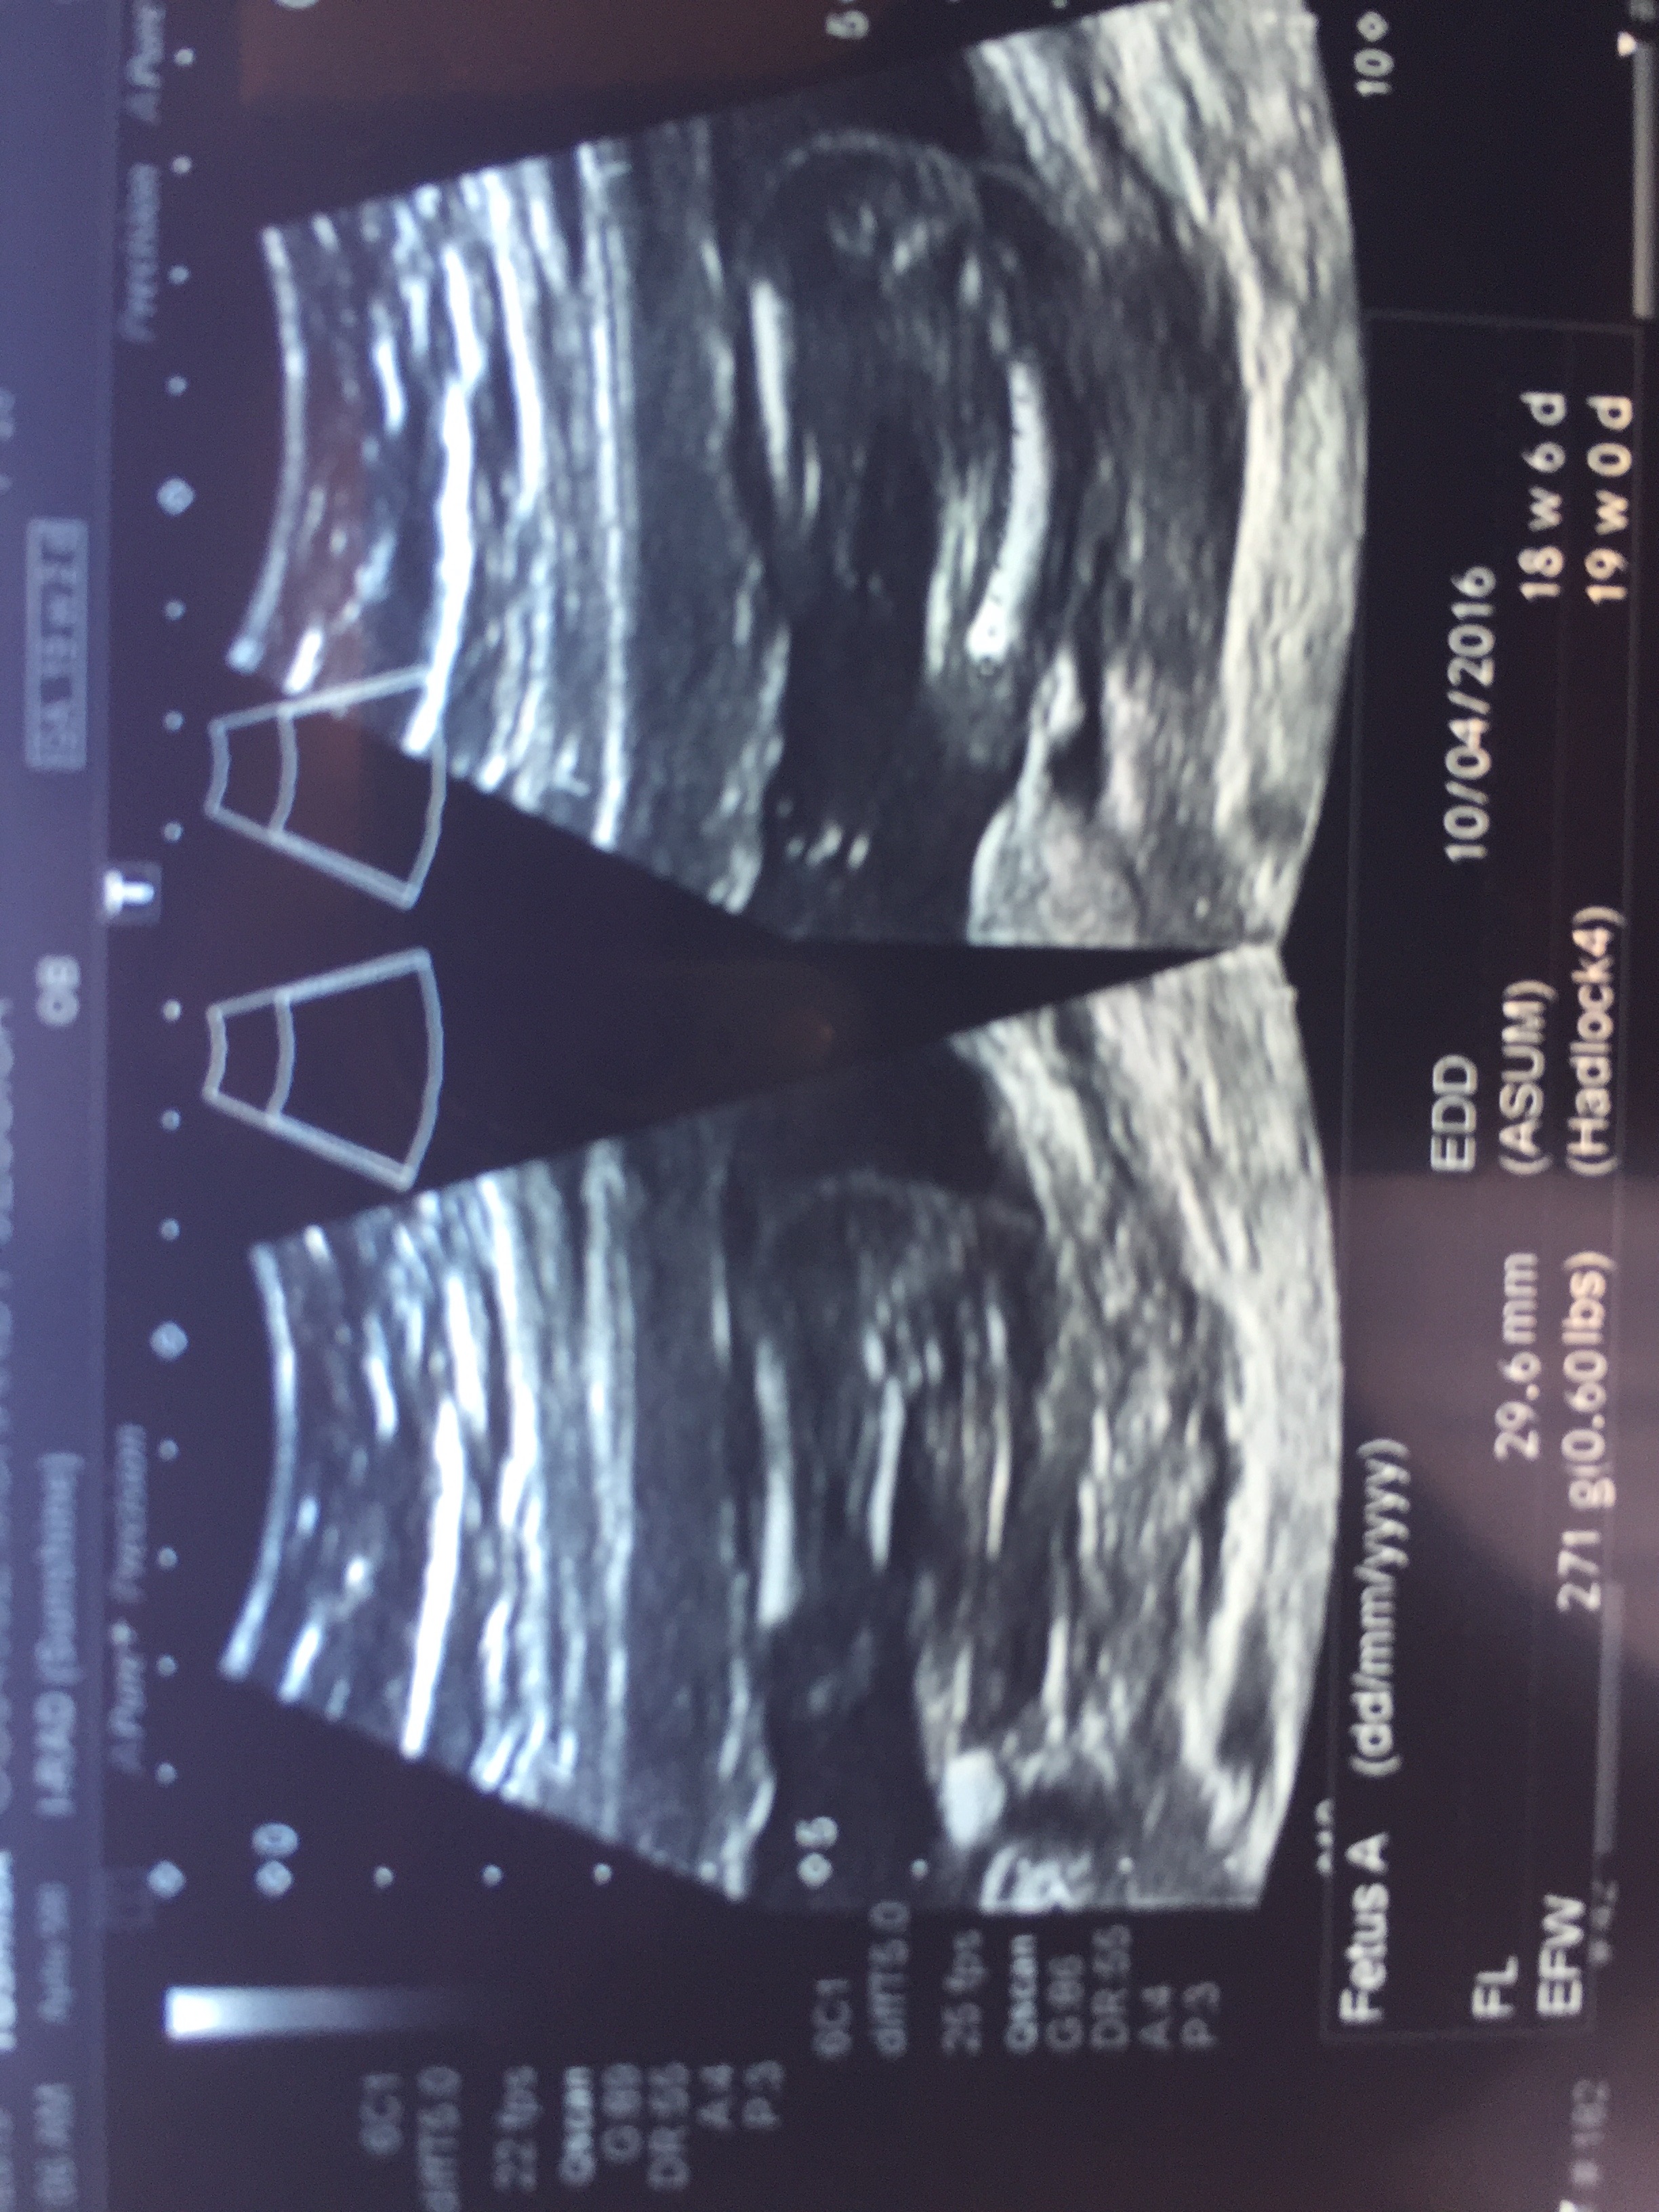

At my 20 week scan. Not sure if that is a nub or not, also Attachment 28608a potty shot not the clearest would love to hear what you think. Tia

I have this one too. Does the angle of the nub still apply at 19 weeks?